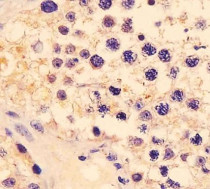

ARG59626 anti-CTAG1A / NY-ESO 1 antibody IHC-P image

Immunohistochemistry: Paraformaldehyde-fixed and paraffin-embedded Human testis blocked with 3% BSA for 0.5 hour at room temperature. Antigen Retrieval: Heat mediation was performed in Citrate buffer (pH 6.0). Samples were stained with ARG59626 anti-CTAG1A / NY-ESO 1 antibody at 1:25 for 1 hours at 37°C.